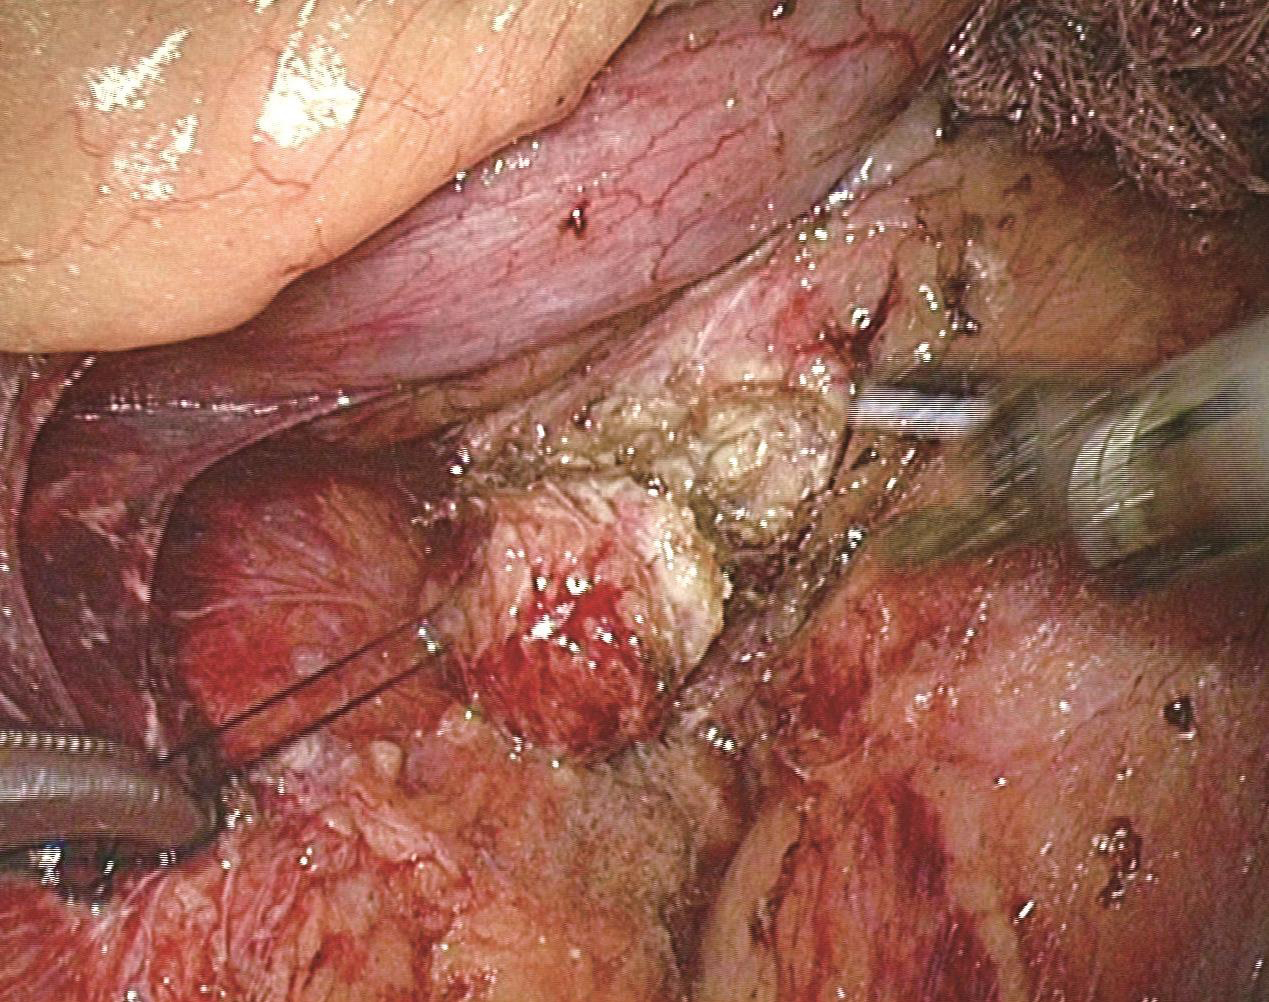

患者取平卧位,头低脚高,右侧稍抬高,取四孔法或五孔法操作;首先将大网膜及横结肠向左上翻起,挡开附近空回肠,显露十二指肠降部及水平部(图6-5);打穿结肠系膜,根据术前定位决定,分离层面(胰头十二指肠背侧或腹侧),钝锐性相结合方法将胰头十二指肠与结肠系膜或肾周筋膜分离(图6-6),显露胰头十二指肠背侧或腹侧(图6-7);明确肿瘤部位,必要时行术中腹腔镜超声定位(图6-8);镜下缝合肿瘤一针作为牵引用(图6-9);超声刀完整剜除肿瘤(图6-10),处理创面;取出标本,送冰冻,留置引流,缝闭切口,术毕。

图6-10 完整剜除肿瘤